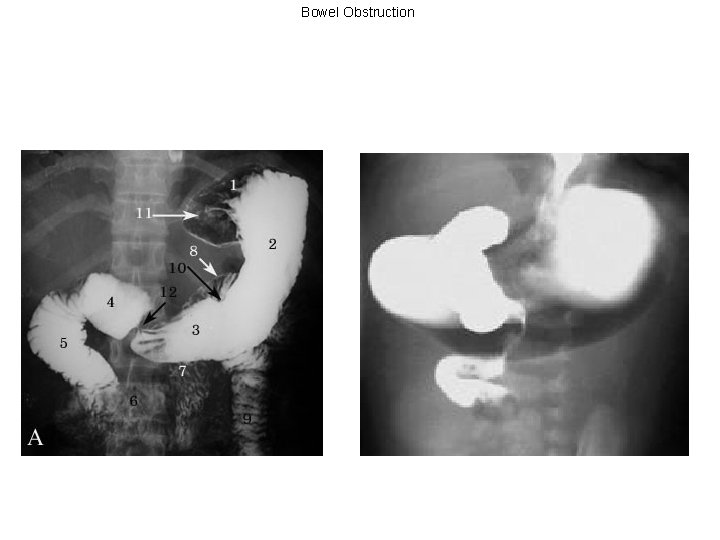

Bowel Obstruction Work-Up • Obstructive series: look for free air, dilated bowel loops, air-fluid levels – Note: if cecal diameter >12 cm, there is a risk of perforation. At 12 -14 cm, the wall tension > perfusion pressure, increasing risk of necrosis • CT scan • Barium enema • UGI series w/SB follow-through

Bowel Obstruction A 74 yo female is evaluated in the emergency room for a small bowel obstruction. Her vitals are 37. 8/ 102/ 110/55/ 20/ 98% 2 LNC. She is distended with mild tenderness to palpation diffusely. Her imaging studies are demonstrated below. What is your next step in management? 1. NPO, NG decompression, IV resuscitation, and serial abdominal exams 2. NPO, NG decompression, IV resuscitation, and plan for immediate exploration 3. NPO and admit for serial abdominal exams 4. None of the above